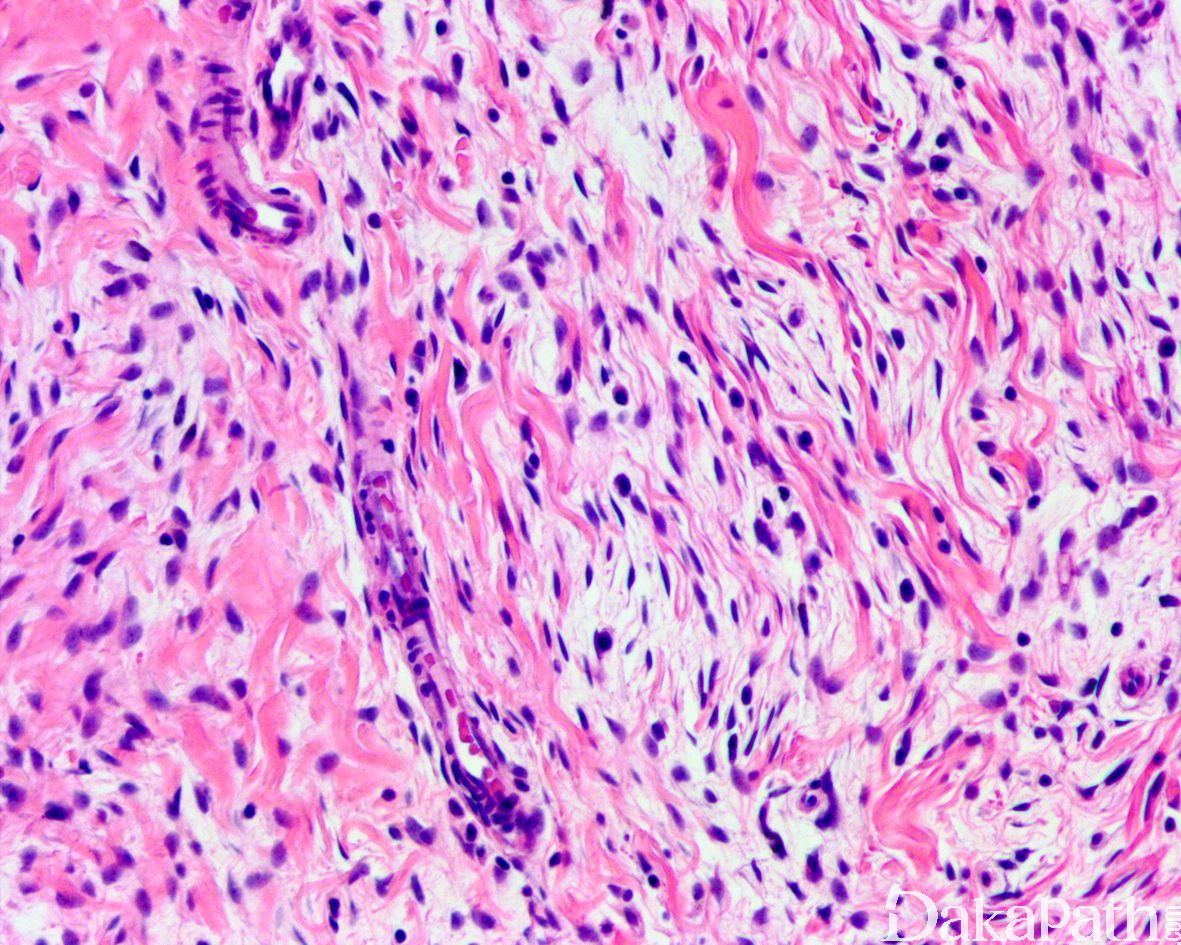

致密的纤维组织由比较成熟的纤维母细胞、肌纤维母细胞和胶原纤维组成,呈纵横交错的束状排列,常呈指状伸入脂肪组织内,组织学类似于纤维瘤病;部分区域可见梭形细胞之间成片的胶原化或瘢痕化以及多核巨细胞沉积,类似于乳腺的假血管瘤样增生或巨细胞纤维母细胞瘤样改变;

原始间叶组织呈结节状分布,由幼稚的短梭形、卵圆形或星状细胞排列成呈疏松的漩涡状、巢状或宽带状包被于富于血管的黏液性基质之间;

瘤细胞形态均教温和,核异型性轻微,罕见核分裂象;